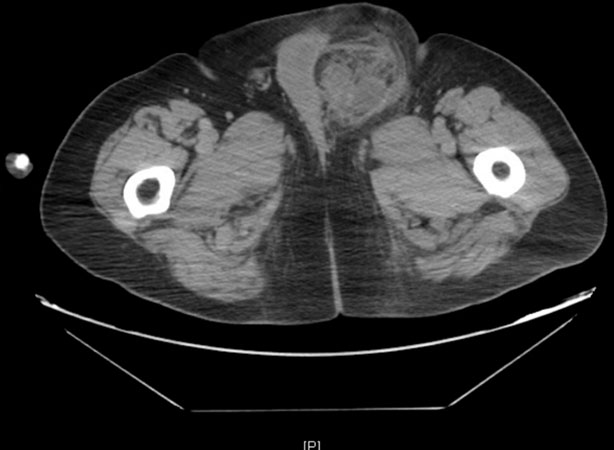

The patient was then referred to our institution. A CT scan of the chest, abdomen, and pelvis showed a mass with no metastatic disease, but it did reveal that the tumor was encroaching on the left testicle with some displacement of the penis (Figure 4). Magnetic resonance imaging (MRI) of the pelvis was performed revealing a large, solid heterogenous soft tissue mass containing macroscopic fat centered in the left inguinal canal with marked thickening of the external spermatic fascia (Figure 5). The imaging appearance was compatible with his given history of sarcoma. It also showed a small, peripherally enhancing fluid collection measuring up to 4 cm in subcutaneous fat superficial to the mass in the left inguinal canal which was thought to be a seroma or abscess related to the biopsy.

Figure 4: Axial CT imaging through the left groin performed after the surgical intervention demonstrated a large infiltrative lesion with internal hemorrhage and necrosis, edema, and fascial thickening. The confounding factors of tumor growth and postoperative hemorrhage result in poor delineation of the residual tumor.